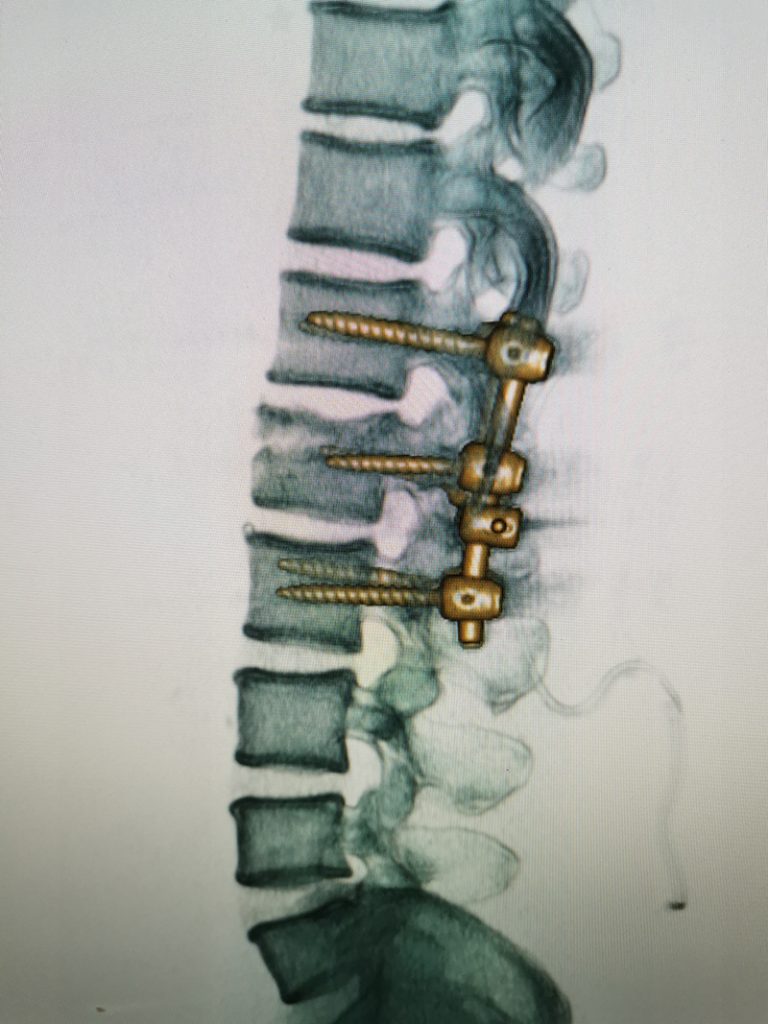

Todas las fusiones espinales usan “injerto óseo,” para ayudar a promover la fusión. En general, se colocan pequeñas piezas de hueso en el espacio entre las vértebras que se deben fusionar. En muchos casos, se utilizar placas, tornillos y barras para ayudar a mantener inmóvil la columna vertebral.